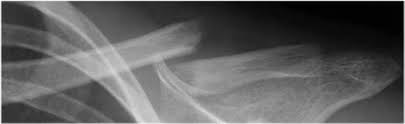

Nun sollten Fäden gezogen werden und es wurde festgestellt dass das Schlüsselbein wieder gebrochen ist. Trotzdem ist die Verletzung vergleichsweise harmlos und gut behandelbar. Ich vermute gute Ärzte haben für die Zeitbestimmung eine Tabelle oder ein Diagramm.

Eine erste Röntgenkontrolle sollte nach ca. Die meisten Brüche sind nach 12 Wochen stabil ausgeheilt. Selten wachsen die Bruchenden nach einer konservativen oder operativen Behandlung nicht richtig zusammen Pseudarthrose.